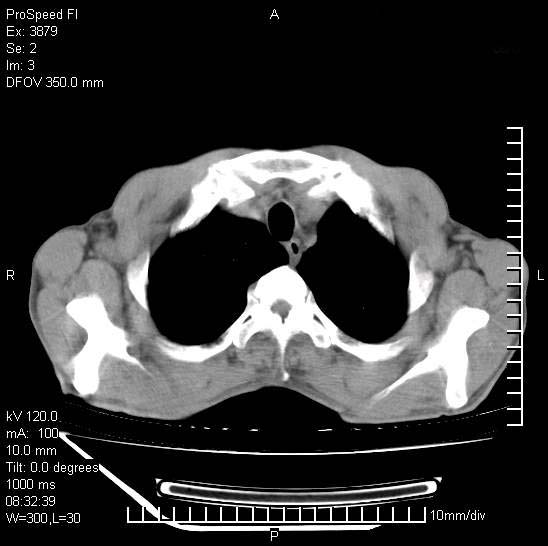

以下是引用37度在2008-6-6 11:20:00的发言:[br]1.包裹性积液,多考虑结核性;[br]2.穿刺术后改变。